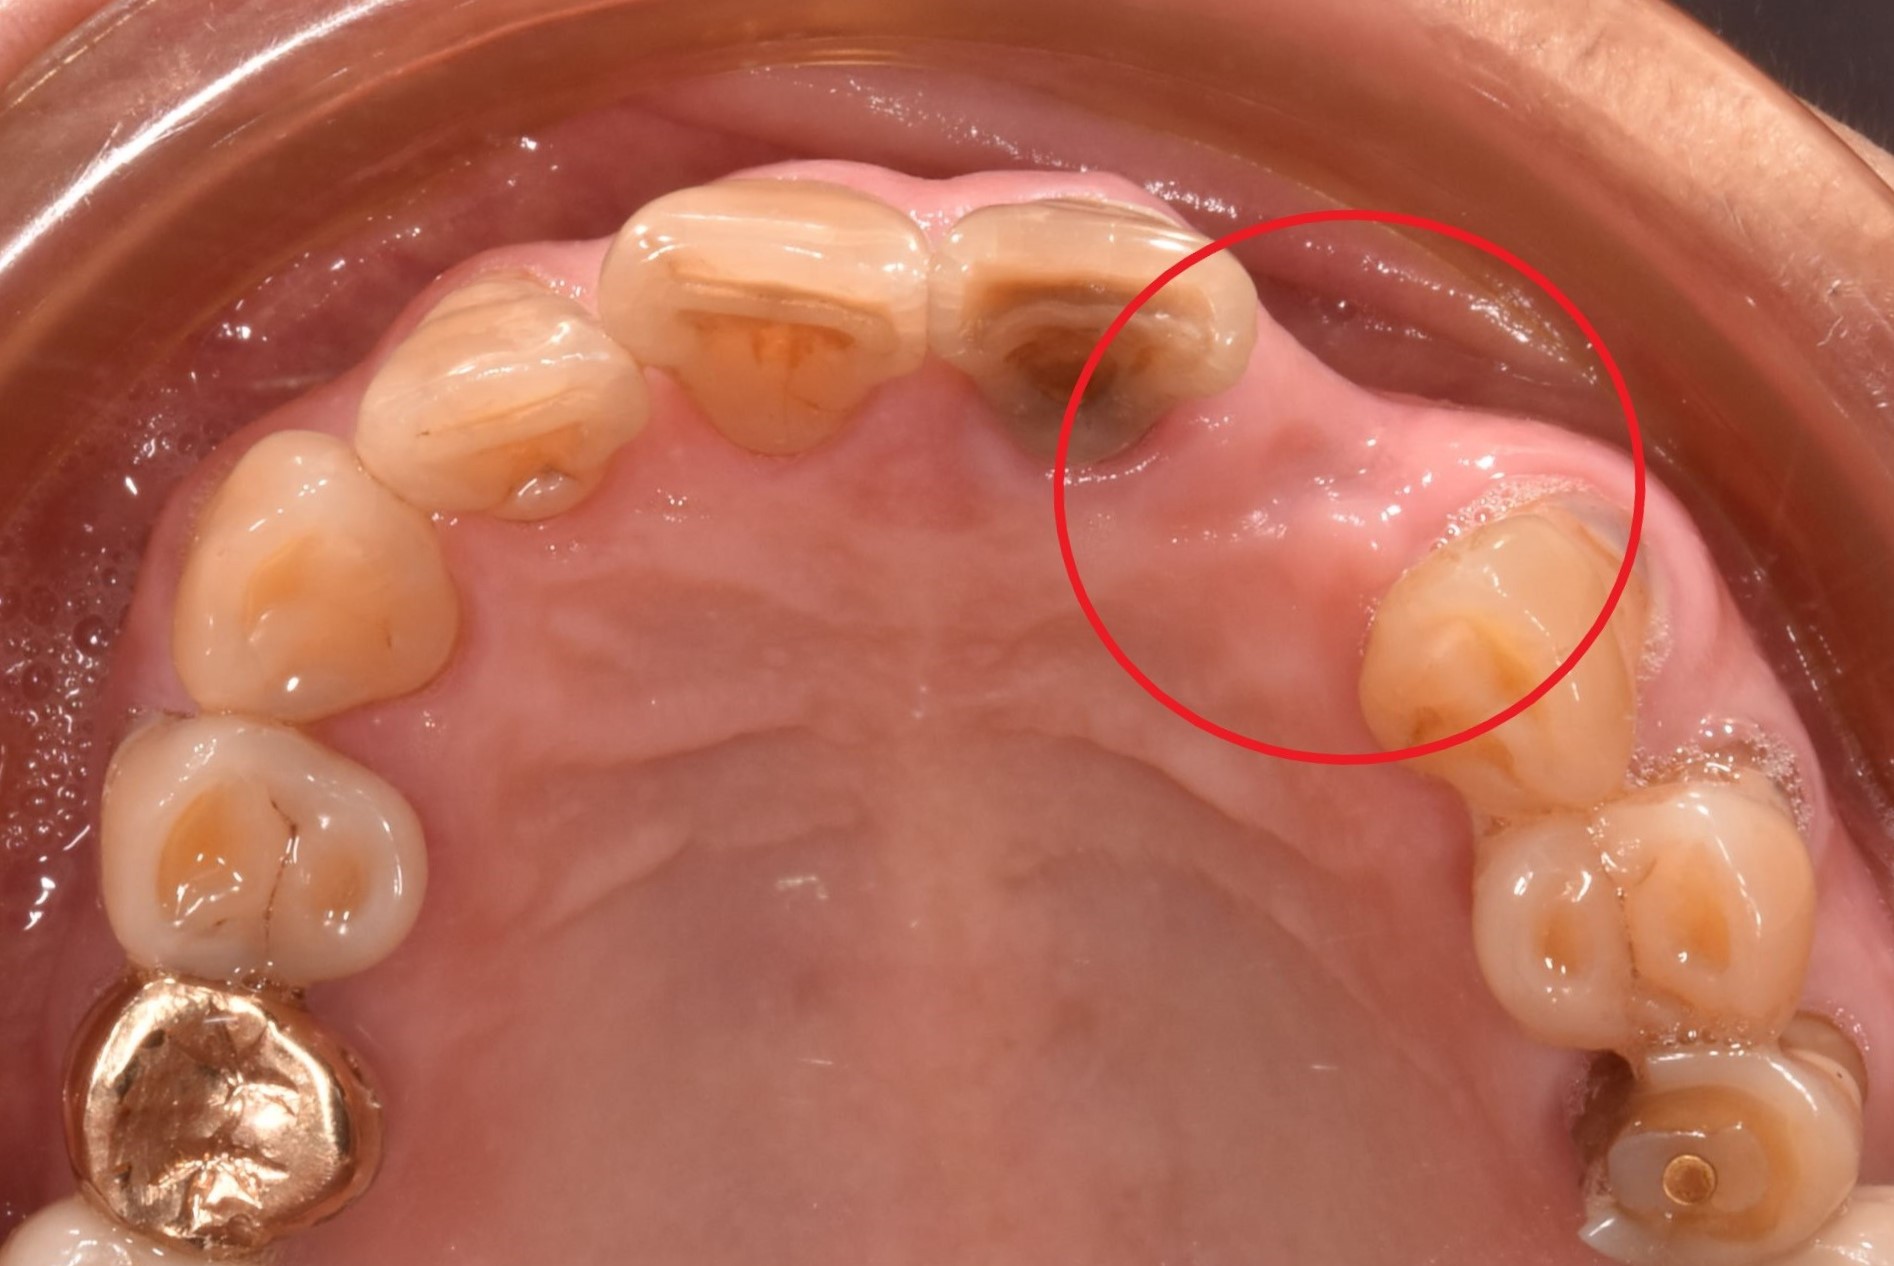

案例一

骨頭明顯凹陷